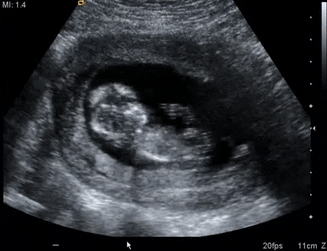

از این هفته به بعد, جنین به سرعت رشد می کند و پزشک احتمالا سونوگرافی جنین را برای بررسی روند رشد جنین پیشنهاد می دهد.

سونوگرافی هفته سیزدهم بارداری اطلاعات مفیدی درباره سلامت جنین می دهد که بسیار مهم است. بنابراین در ادامه با ما باشید تا از علت انجام سونوگرافی در هفته ۱۳بارداری و نحوه انجام آن مطلع شوید:

سونوگرافی که در هفته سیزدهم انجام می شود می تواند جزئیات زیادی را درباره جنین مشخص کند. شما می توانید ضربان قلب جنین تان را بشنوید و همچنین متوجه برخی از ارگان هایش که رشد نموده شوید

در سونوگرافی های اولیه شما متوجه شده بودید که سر جنین در مقایسه با دیگر ارگان ها بزرگ تر و غالب تر است اما اکنون بخش های دیگر بدن جنین به سرعت در حال رشد هستند و اندازه سر در حال متناسب شدن با بدن است. سونوگرافی می تواند هرگونه ناهنجاری و دیگر جزئیات نمو جنین را مشخص کند.